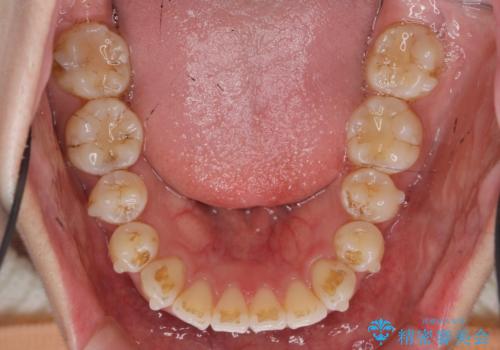

- 前歯の噛み合わせの開きの改善を求めて来院されました。

奥歯はほとんど動かさず(奥歯の噛み合わせはほとんど変えず)前歯のIPR矯正でガタつき前突感(出っ歯感)の改善を計画します。

ほとんど前歯のみの矯正治療であることからトータル14枚のマウスピースで並べるインビザラインライトによる治療を行います。